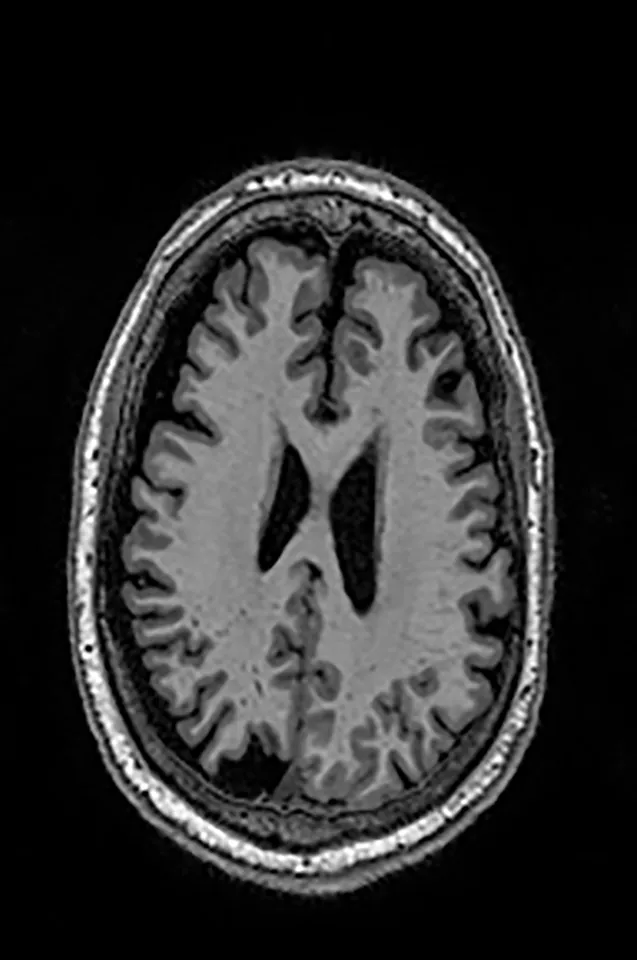

2.2 Datasets

Two different datasets (the Alzheimer’s dataset (four classes of images) and ADNI_Extracted_Axial) were used to validate the proposed approach. Both datasets are publicly available (https://www.kaggle.com/datasets/tourist55/alzheimers-dataset-4-class-of-images and https://www.kaggle.com/datasets/katalniraj/adni-extracted-axial; accessed November 13, 2023). The specifications of this dataset are listed in Table 1.